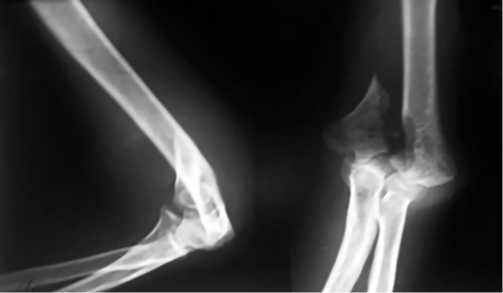

Чтобы проиллюстрировать последовательность применяемого нами алгоритма лечения, приведем пример пациентки У. (44 года), которая получила травму в результате дорожно-транспортного происшествия (диагноз: оскольчатый перелом левой плечевой кости в нижней трети со смещением отломков).

При поступлении в отделение назначен план обследования пациентки: анализы для выполнения анестезиологического пособия, электрокардиограмма, рентгенограммы грудной клетки, левого плеча (рис. 4), компьютерная томография правого плеча (рис. 5), консультация терапевта, невролога, анестезиолога-реаниматолога.

Рис. 4. Рентгенограмма левого локтевого сустава при поступлении

Fig. 4. X-ray of the left elbow joint upon admission